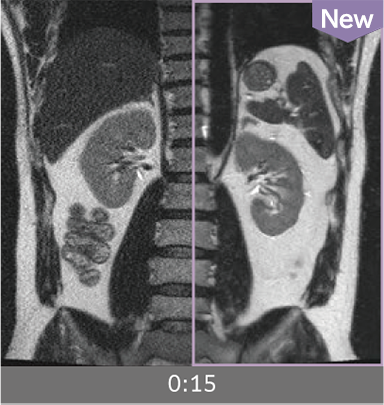

Images can be obtained at high speed by combining two technologies: IP-RAPID, which reduces imaging time while maintaining image quality, and Advanced Reconstruction to improve image quality.

Under-sampling reduces imaging time, and iterative reconstruction with IP-RAPID reduces noise and artifacts.

In addition, Advanced Reconstruction further eliminates noise and produces images that are easier to use in making a diagnosis.